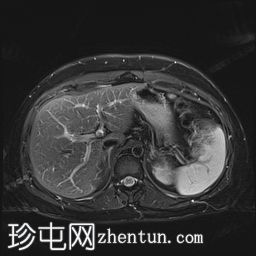

轴位T2加权像

脂肪抑制序列

T1低信号,T2低信号为主的脾脏肿块,内部可见T2高信号分隔,呈进行性强化。肿块中央可见星状瘢痕。

脾脏硬化性血管瘤样结节性转化(SANT),9.8 cm肿块

顾名思义,脾脏硬化性血管瘤样结节性转化(SANT)是一种纤维性血管病变。本病例展示了SANT的一些典型影像学特征,包括边界清晰的病灶,中央可见瘢痕,以及呈放射状进行性强化。这些特征使得术前MRI诊断较为明确。尽管SANT是一种良性病变,但大多数患者仍需行脾切除术以明确病理诊断。